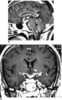

Tuberculosis of meninges

Tuberculous meningitis is also known as TB meningitis or tubercular meningitis. Tuberculous meningitis is Mycobacterium tuberculosis infection of the meninges—the system of membranes which envelop the central nervous system. [Source: Wikipedia ]